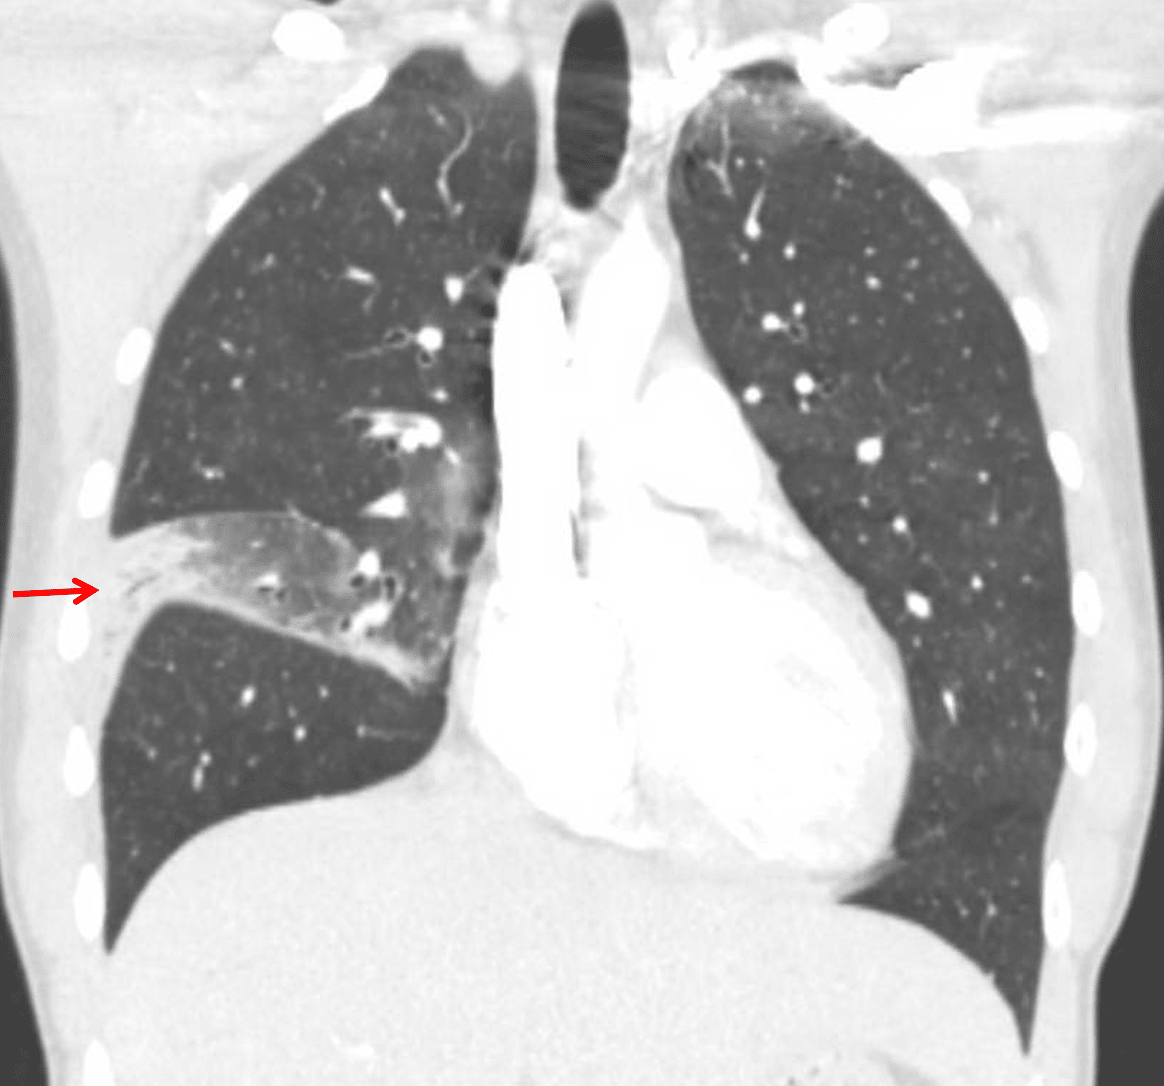

- Mild volume loss in the right middle lobe with groundglass opacification throughout the lobe and consolidation in the lateral segment

- Mild dependent right lower lobe atelectasis

- Small right pleural effusion

- This case has coexisting pneumonia and atelectasis in the right middle lobe, which accounts for the confusing volume loss not typically seen with infection alone

Lobar pneumonia: consolidation in the lateral segment of the right middle lobe with associated volume loss in the right middle lobe.